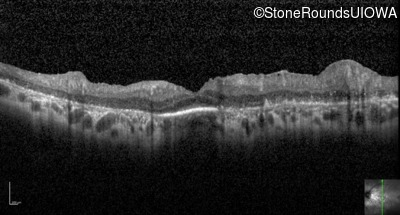

Optical Coherence Tomography - Right - 20/70

Exemplar / OCT Stack